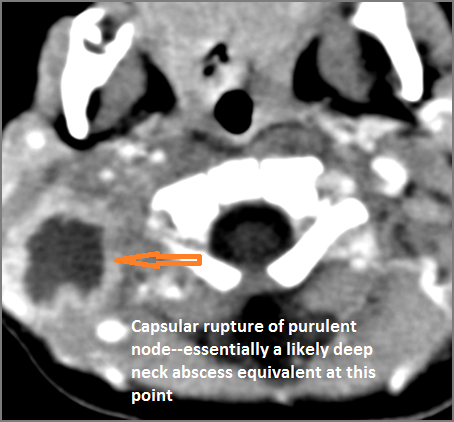

If there is suppurative cervical adenopathy the purulent material outside the lymph node(s) capsule(s). [Yes/No]